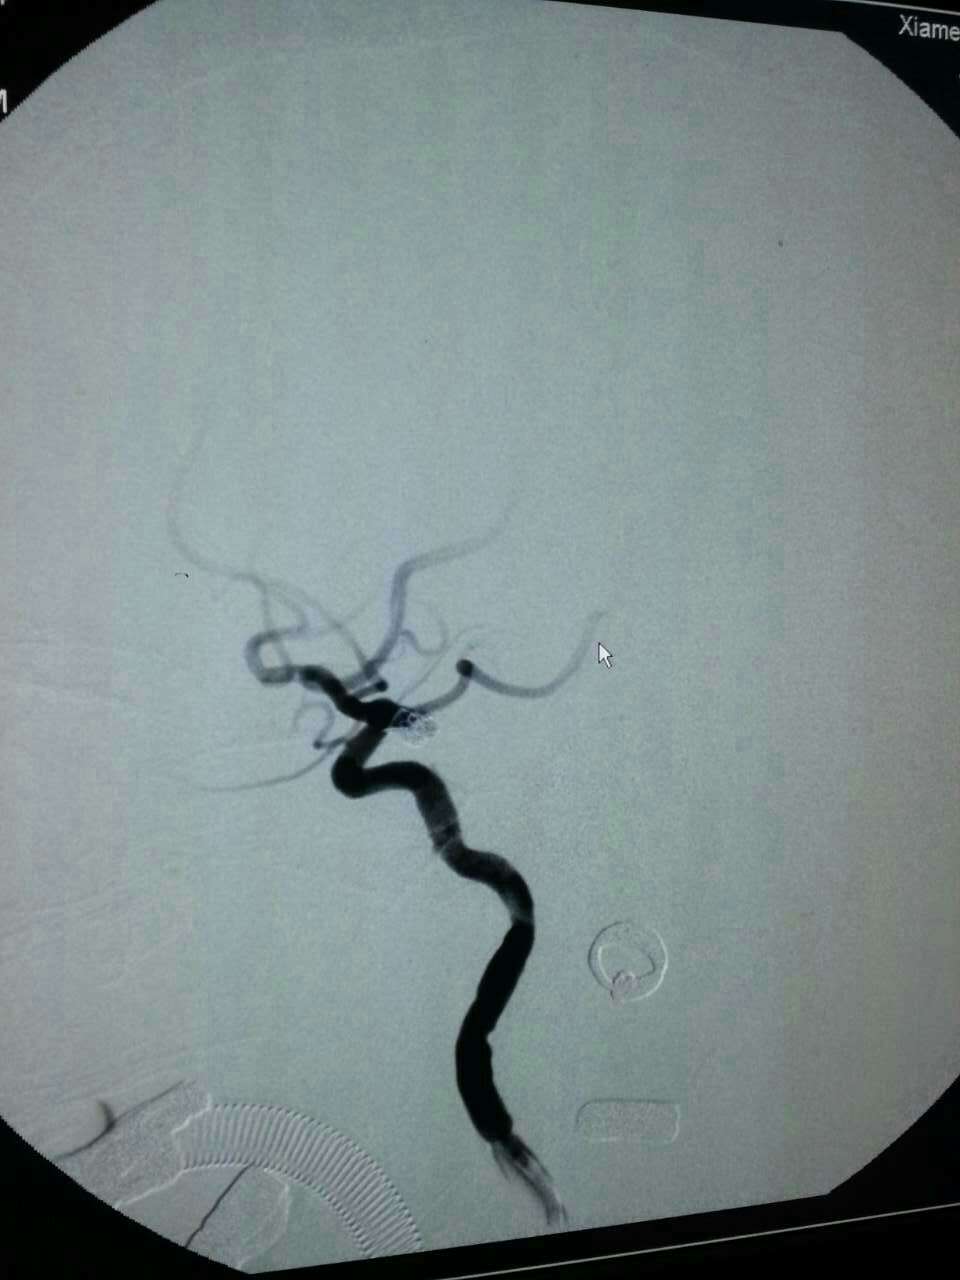

神经外科每年应用介入栓塞技术抢救颅内动脉瘤破裂患者上百例。昨天晚上,陈金龙副主任医师、何雪阳等技术团队又成功抢救来自同安莲花一位80岁叶女士,大量蛛网膜下腔出血,手术顺利,现患者已清醒,可自行进食。